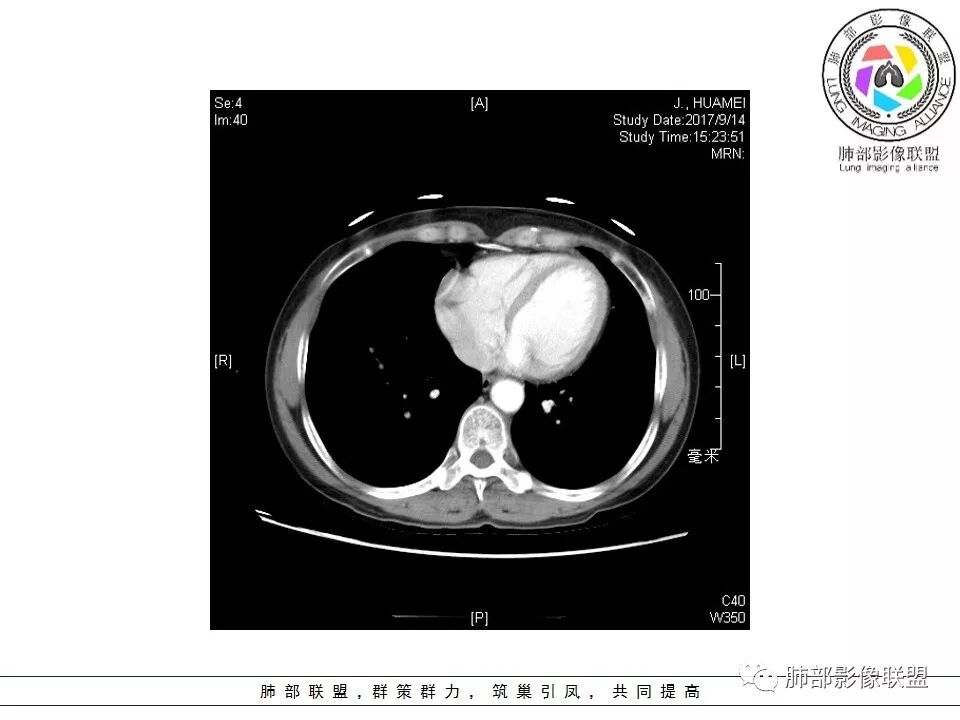

晨读:右肺下叶肿块影,浅分叶,不均匀强化,有血管穿行其中,考虑肺癌,神经内分泌肿瘤可能性大。

右肺下叶结节,边缘毛糙,内支气管推移,有血管贴行,小细胞肺癌?

晨读:右下肺前基底段支气管亚段分叉处占位,密度均匀、中度均匀强化,结节近边缘有支气管、血管穿行,结节边缘较光滑、有细短毛刺、无分叶,结节周围无卫星灶。考虑:PSP,鉴别:小细胞肺癌、不典型错钩瘤

内部支气管扩张,穿行血管形态自然,支持malt。

轻度分叶,支气管穿行,轻中度强化,血管漂浮,考虑MALT

右肺下叶前基底段肿块,边缘不光滑,毛糙,内见充气支气管征,边缘有浅分叶,肿块周围无病灶,排除了结核。增强扫描明显强化,内见血管影,考虑恶性肿瘤。女性,腺癌多见。

淋巴瘤与小细胞癌鉴别,纵隔内没有肿大淋巴结、结节边缘比较毛糙,淋巴瘤放第一位。

病灶呈圆形,轻度分叶,内见血管及支气管影,考虑MALT。

右肺下叶前基底段结节 边缘磨玻璃密度较清 内部支气管扩张,轻中度强化 穿行血管形态自然,支持淋巴瘤。

晨读:右肺下叶肿块影,浅分叶,边界清,轻度均匀强化,血管自然穿行,NSE偏高,考虑小细胞肺癌!

中年女性,右肺下叶前基底段肿块,轻度分叶,有棘样突出,充气支气管征穿行并形成脐凹征。增强扫描中度强化,内见血管影,血管壁毛糙,考虑恶性,腺癌?小细胞肺癌?

晨读,右肺下叶前基底段实性结节,边缘膨隆,可见多发浅分叶,结节内密度均匀,增强后呈轻度均匀强化,血管穿行走形自然,首先考虑恶性肿瘤,内有支气管穿行,淋巴瘤可能大,腺癌待排。

右肺下叶肿块,边缘光滑,浅分叶,膨隆明显,局部有清楚的ggo,考虑恶性,类癌首可能,鉴别腺,PSP。

中年女性,右下类圆形肿块,部分膨胧,边缘浅分叶,脐凹,内见血管穿行,增强轻中度强化,叶间胸膜结节?考虑腺癌,内有支气管穿行,鉴别淋巴瘤。

右肺下叶肿块影,边缘光滑,彭隆,浅分叶,内见支气管通过,增强明显强化,内见血管影,考虑恶性肿瘤,神经内分泌癌,鉴别淋巴瘤。

中年女性,体检发现,病史及化验无特殊。胸部CT右肺下叶前基底段见一类圆形结节,边界清楚,分叶不明显,边缘呈锯齿状改变,病灶内支气管穿行,无扩张及扭曲,增强扫描病灶明显均匀强化,内见穿行血管影,走形无扭曲。考虑粘膜相关性淋巴瘤可能。鉴别炎性假瘤、腺癌及小细胞癌。

胸CT:右肺下叶前基底段占位性病变,内可见支气管穿过,病灶边缘不规则,呈浅分叶,未见明显毛刺。纵隔窗可见病灶密度相对均匀,增强可见病灶强化,内可见血管增粗,边缘模糊,总体考虑恶性,腺?。良性疾病鉴别错构。

右下肺类圆形实形结节,边缘膨隆,浅分叶,其内可见支气管及血管影走行,轻度强化,考虑恶性病灶,淋巴瘤?类癌?

边缘彭隆,还是考虑肿瘤,支气管通入,肺内原发,支气管自然穿行稍扩张,血管比较自然同行,漂浮征,增强后整个比较均匀无明显坏死,淋巴瘤首选。恶性应该没有问题,建议穿刺。

这个病灶边缘还是有一点点恶性征象,有分叶,似乎有点地方还有一些小毛刺样感觉

部分区域整体以膨隆为主,部分区域稍收缩

内部支气管走形非常自然,达远端稍扩张;内部血管穿行也非常自然

内部密度比较均匀,我们一般来说,首先良性肿瘤不支持,因为它里面的血管走形太自然了;然后就是炎性病变跟恶性肿瘤,但是它的边缘膨隆比较厉害,有些地方还毛刺,不是很清楚,倾向一个恶性病变

恶性的血管穿行自然,包括支气管稍扩张,最常见还是淋巴瘤,它强化比较均匀;

粘液腺癌一般支气管扩张比较罕见,这个密度及强化太均匀,不是很符合,所以把淋巴瘤放前面,癌待排;

方向定在恶性的,炎性病变不是很符合